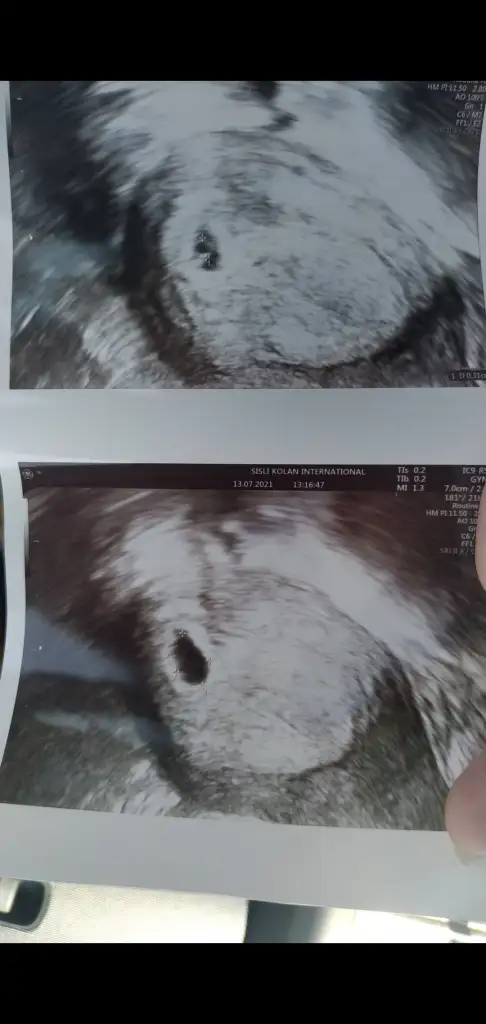

Vajinal bu 13 temmuzda gitmiştim en sonn şu beyaz yerde yolk kesesi 3mm bebekte yavaş yavaş buradan görüncek dedi ve reklamlar 😂

Eklentiler

• Screenshot_2021-07-29-14-31-39-116_com.miui.gallery.webp

Screenshot_2021-07-29-14-31-39-116_com.miui.gallery.webp

19,3 KB · Görüntüleme: 67